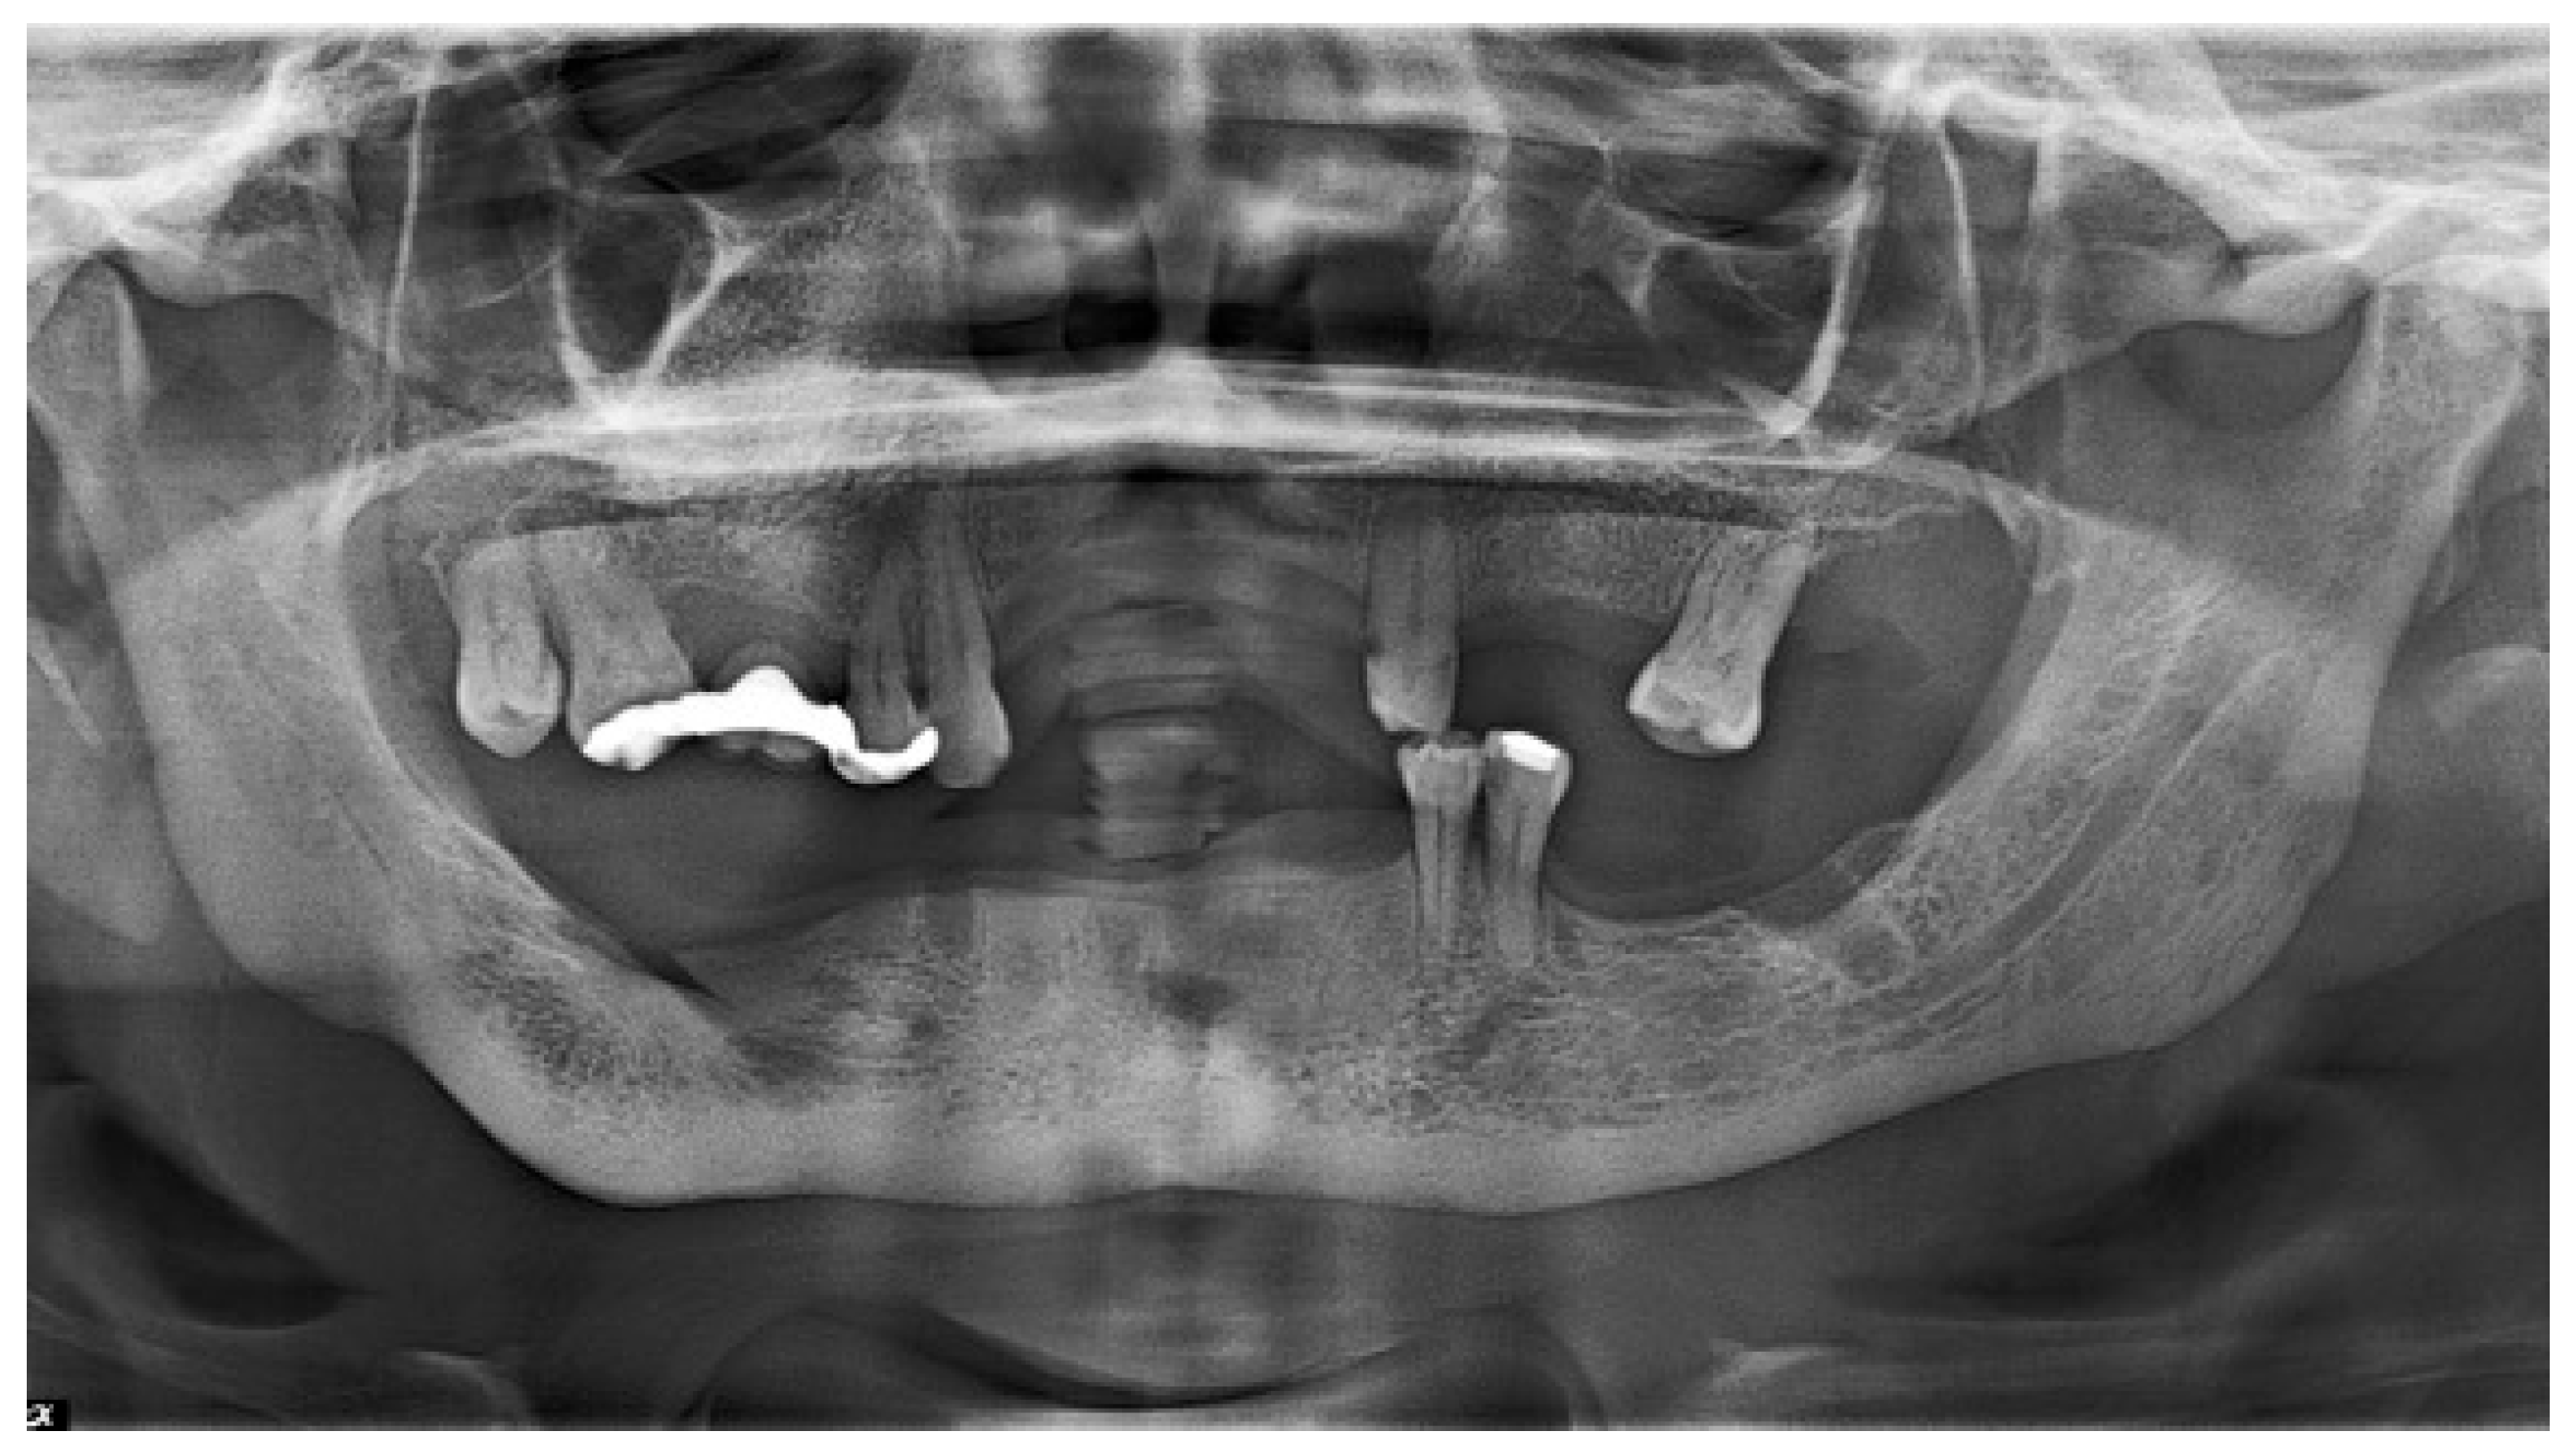

2.2. Treatment Procedures and Histopathological Results